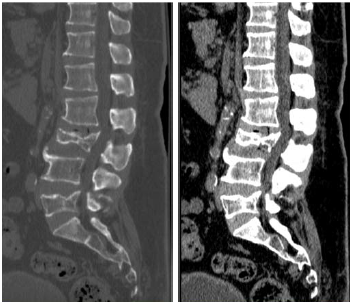

Um paciente de 62 anos de idade foi vítima de queda da própria altura há cerca de três horas. Ele chegou ao pronto-socorro queixando-se de dor lombar de moderada intensidade.

De acordo com a AOOTA spine, é correto classificar a fratura de L3 como do tipo

Provas

Um paciente de 62 anos de idade foi vítima de queda da própria altura há cerca de três horas. Ele chegou ao pronto-socorro queixando-se de dor lombar de moderada intensidade.

No caso descrito, foi solicitada uma TC da coluna lombar, conforme apresentado. Esse exame mostra fratura de

Provas